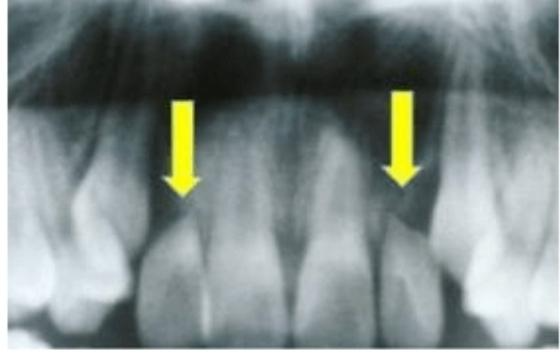

2. 치근 흡수

두번째로 치근 흡수 입니다. 치근, 즉 치아의 뿌리 부분이 흡수되어 버리는 겁니다.

이는 첫번째인 잇몸 퇴축과 반대되는 현상입니다. 치아 자채가 내려앉아 잇몸에 파묻히게 됩니다.

가장 흔한 부작용이고, 이 또한 치아가 흔들거리며 빠지게 됩니다.